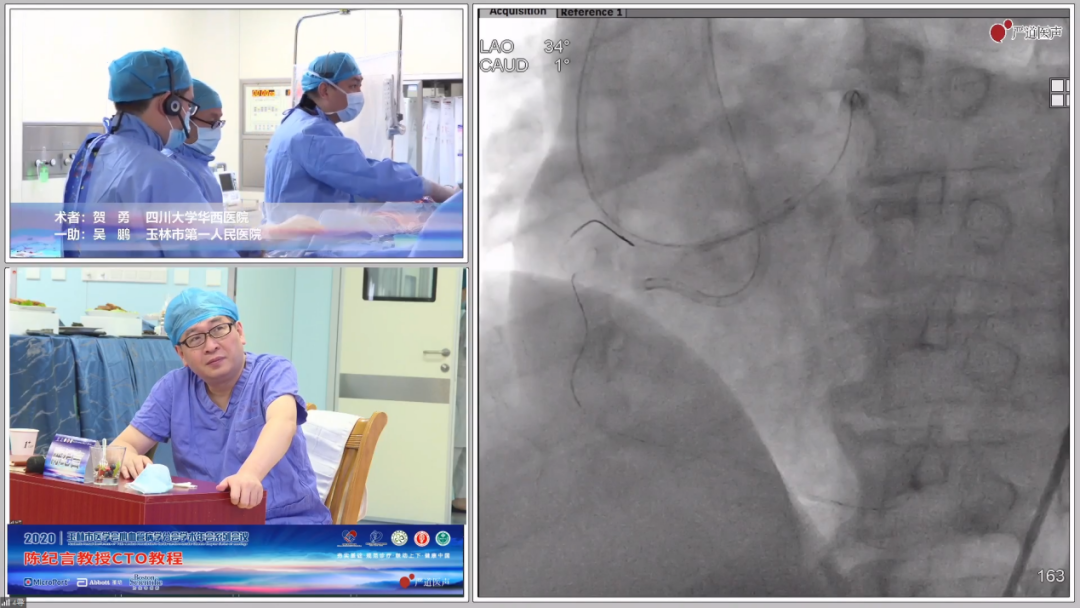

手术演示精彩转播

手术过程

逆向尝试

正向尝试

IVUS辅助下的reverse CART

IVUS指导下的reverse CART